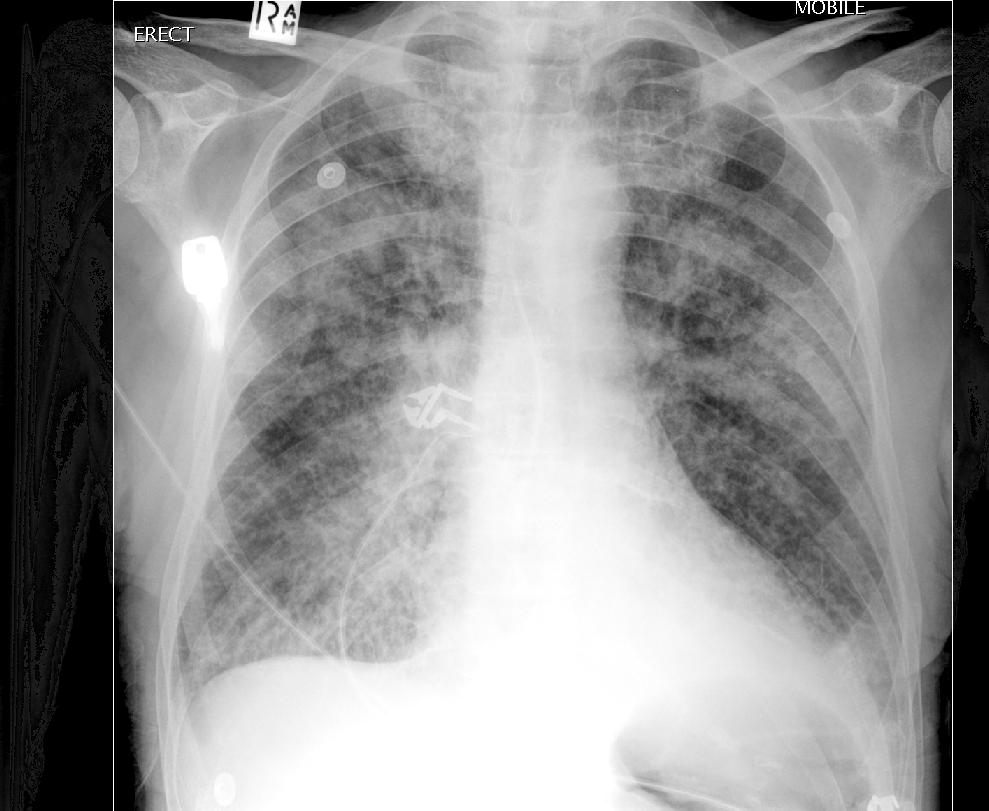

Рентгенография

Рентгенография грудной клетки и по сей день считается наиболее полезной с практической точки зрения модальностью позволяющей оценить отек легких [3-4]. Признаки используемые для оценки:

- признак оленьих рогов / венозное полнокровие верхних долей

- увеличение значений кардиоторакального индекса / оценка увеличения тени сердца полезна для поиска причины

- признаки интерстициального отека:

- расширение корней легких с нечеткими контурами (потерей структурности) в виде «крыльев бабочки»

- септальные линии / линии Керли

- утолщение междолевых щелей

- перибронхиальные муфты

- признаки альвеолярного отека легких:

- множественные расплывчатые, сливающиеся между собой очаговые тени

- плевральный выпот и скопление жидкости по ходу междолевых щелей

В целом прогрессирование рентгенологической картины отражает повышение давления измеряемого при помощи катетера в дистальной части легочной артерии (PCWP).![]()